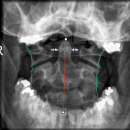

Dens (Spezialaufnahme)

- 2) Atlantoaxialer Übergang: Distanz Dens-Massa lateralis ? (Distanz 3-5mm = V.a. parteielle Ruptur des Lig transversum; Distanz > 5mm = V.a. komplette Ruptur des Lig. transversum)

Einteilung der Densfraktur nach Anderson und D`Alonso

- Typ 1: Fraktur des oberen Anteils des Dens (stabile Fraktur!)

- Typ 2: Densbasis-Querfraktur (instabile Fraktru!)

- Typ 3: Densbasisfraktur mit Ausdehnung auf den Axiskörper (stabile Fraktur!)

- CAVE: Os odontoideum

Einteilung der Atlasfraktur

- Typ 1: Vordere Atlasbogenfraktur

- Typ 2: Hintere Atlasbogenfraktur

- Typ 3: Vordere und hintere Atlasbogenfraktur (Jeffersonfraktur)

- Typ 4: Fraktur der Massa lateralis

- Typ 5: Proc. transversus Fraktur